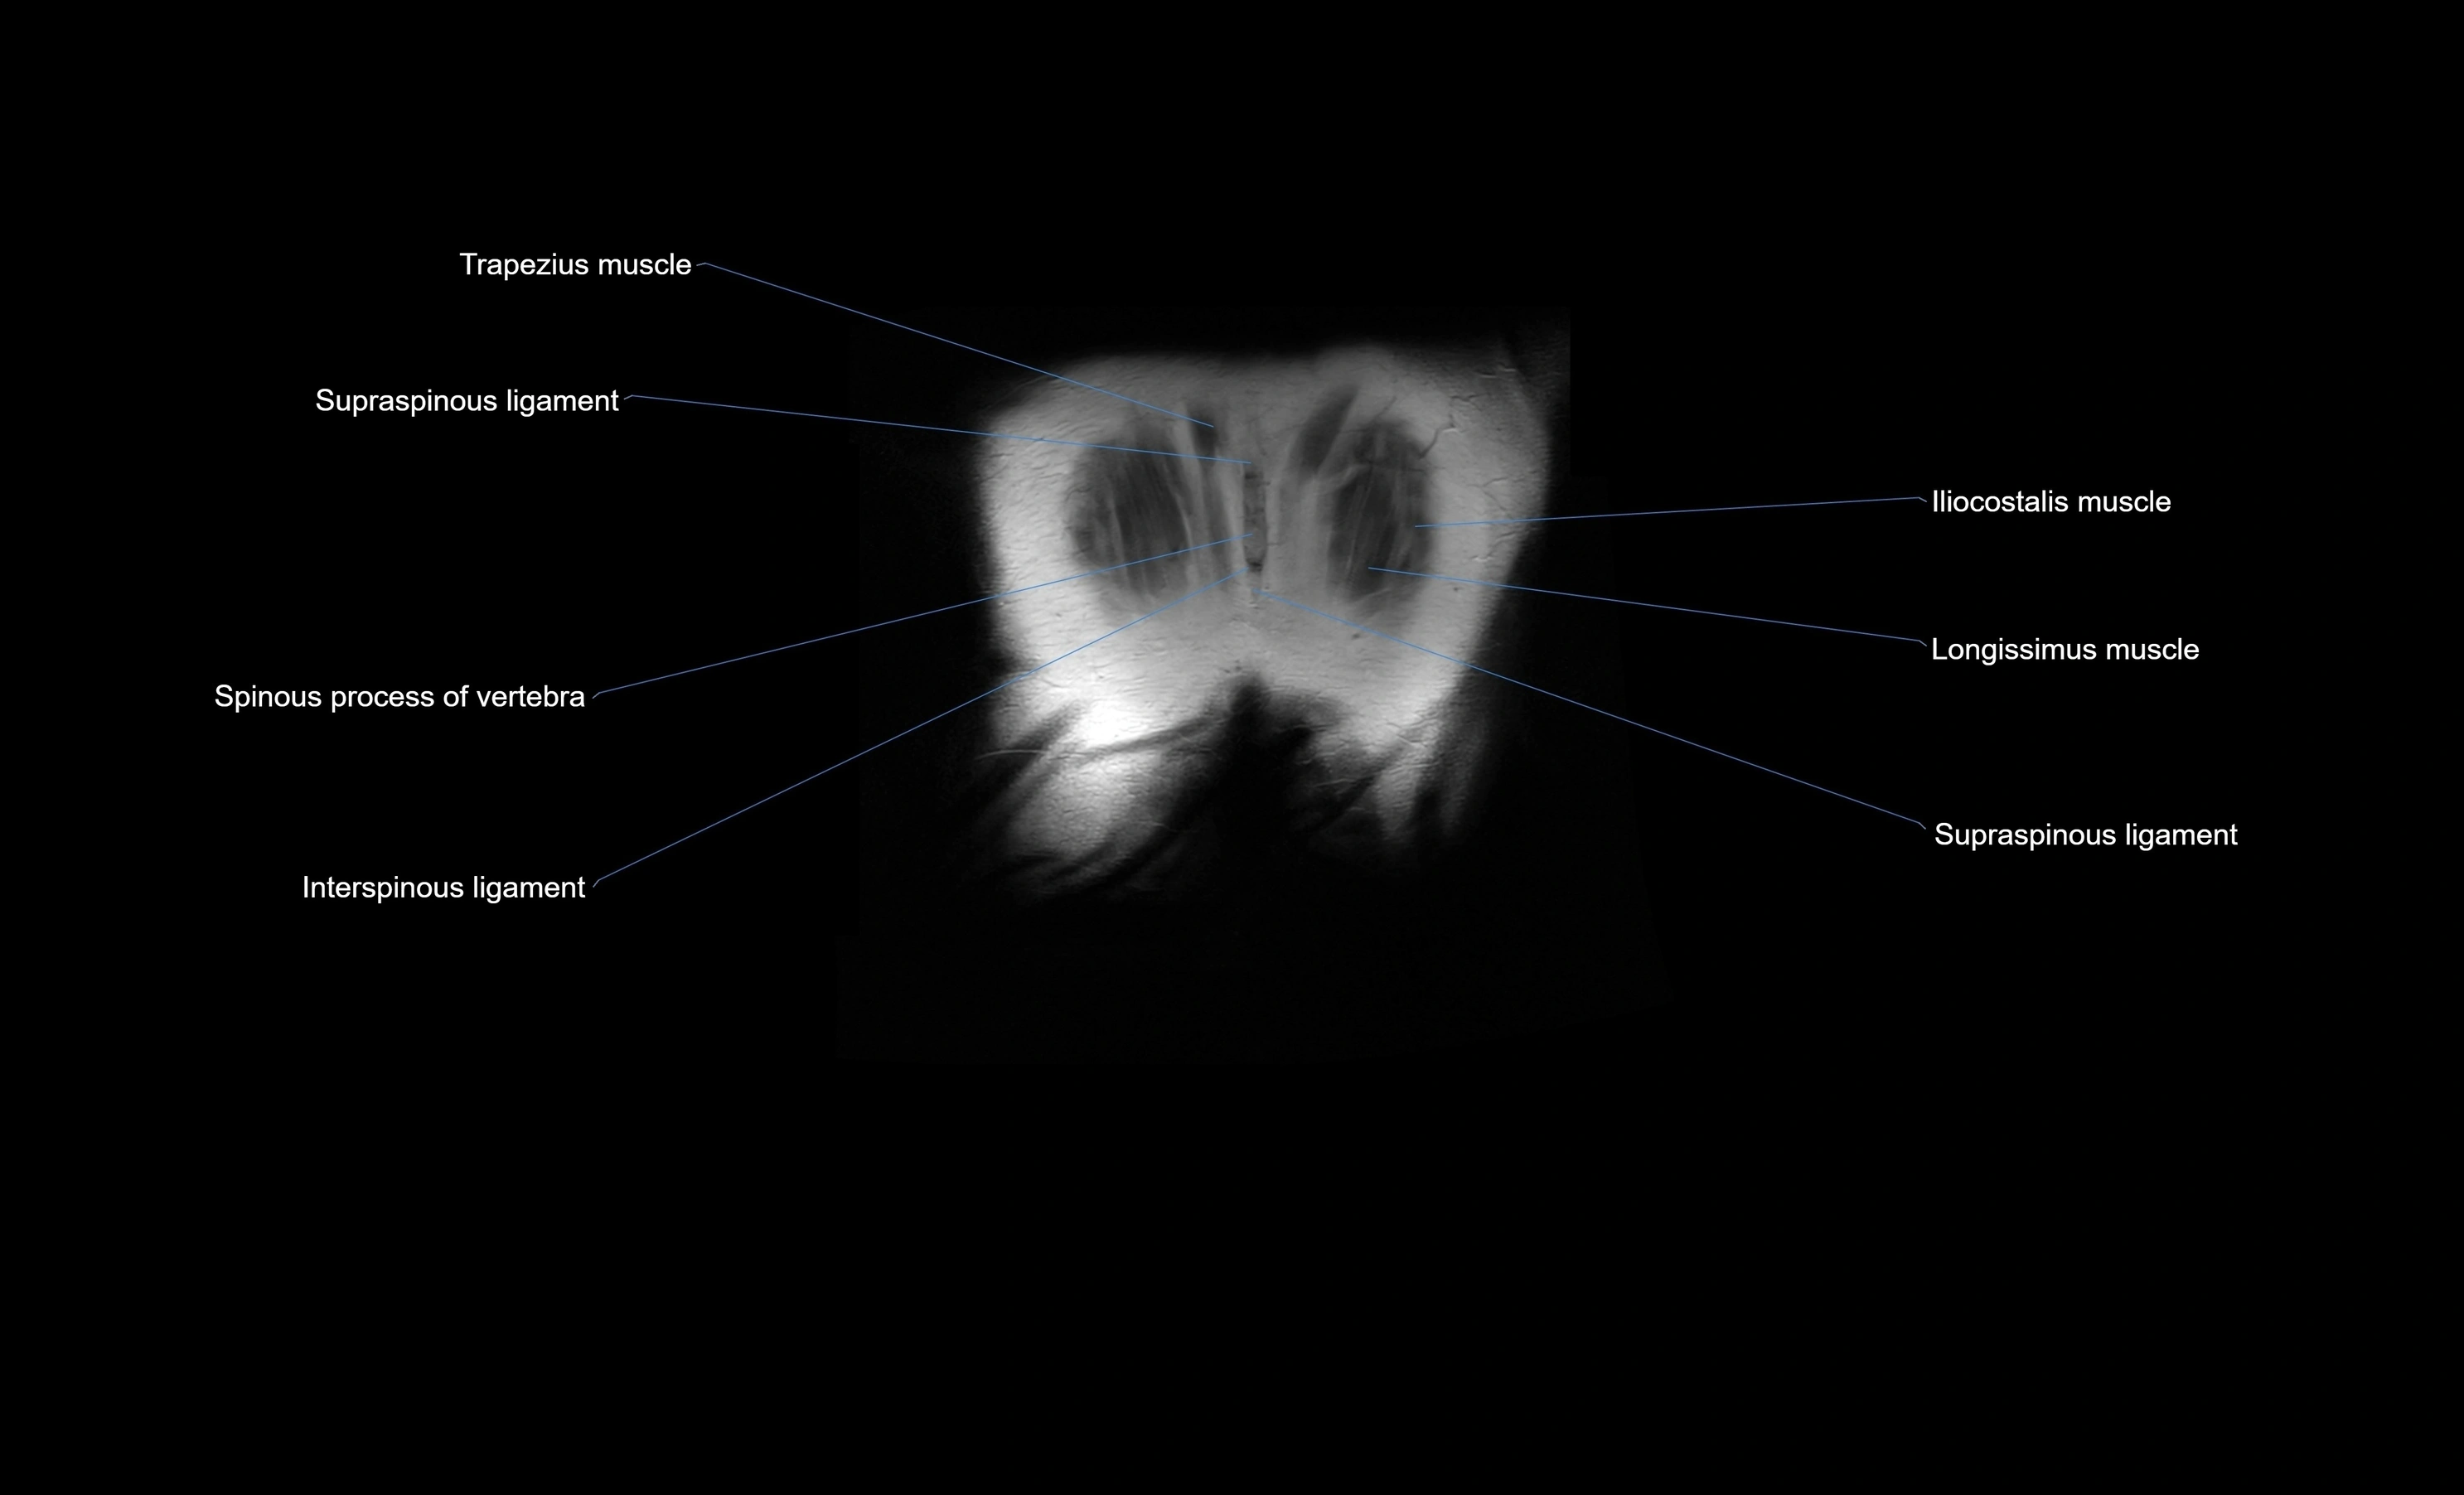

- Iliocostalis lumborum muscle

- Interspinous ligament

- Longissimus thoracis muscle

- Spinous process of vertebra

- Supraspinous ligament